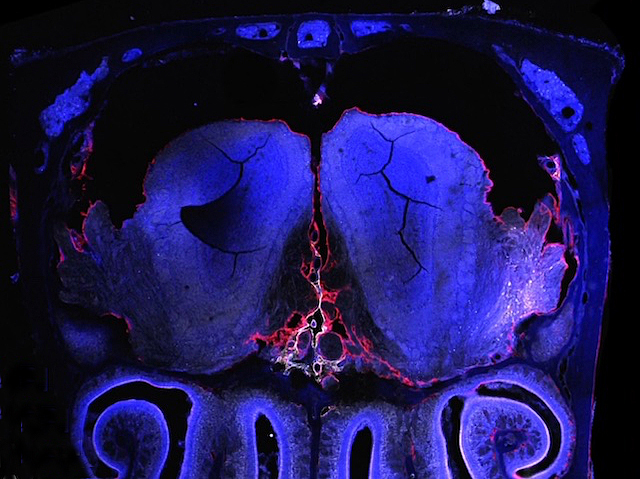

Head Sore Trails

The confluence of olfactory (smell) nerves, cerebrospinal fluid and ethmoid (between brain and nasal cavity) bone marrow in the skull is a dynamic immune microenvironment – insights for understanding and treating neuroinflammatory disease